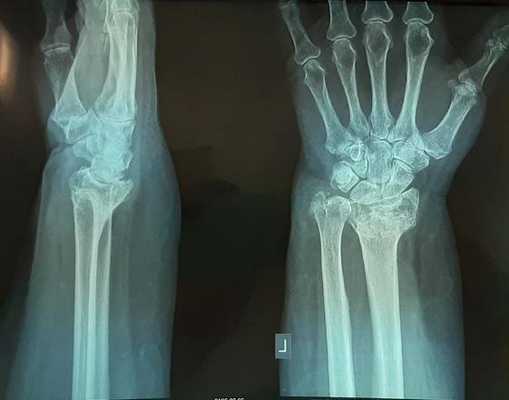

На представленной рентгенограмме не тренированный глаз может вообще не увидеть перелома, хотя врач травматолог и квалифицированный рентгенолог заметят насколько «просела» суставная поверхность лучевой кости, и отметят, что она развёрнута в тыльную сторону на 10 градусов (в норме она должна смотреть в ладонную сторону). Если присмотреться повнимательнее становятся видны линии перелома.

Несмотря на это многие травматологи продолжают лечить такие переломы методом гипсовой иммобилизации. В конечном итоге перелом срастается с грубым смещением, суставная поверхность оказывается развёрнута в тыльную и лучевую сторону.

Формируется грубый артроз лучезапястного сустава. Клинически это проявляется визуально деформацией в области лучезапястного сустава, ограничением амплитуды движений, болью при физической нагрузке.